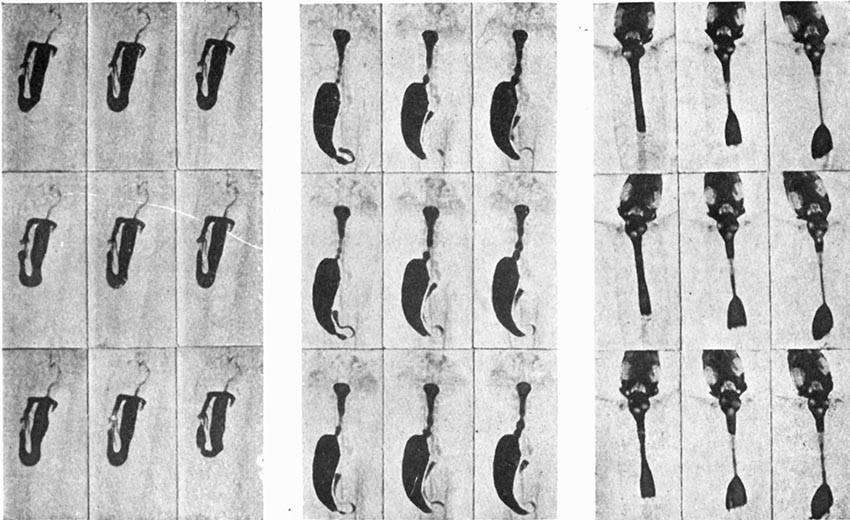

| Water Beetle attacking a Worm | 85 |

| A wonderful X-ray Film made by M. J. Carvallo | 148 |

| Moving X-ray Pictures of the Digestion of a Fowl | 149 |

| Stomach and Intestine of a Trout | 152 |

| Digestive Organs of the Frog | 152 |

| Lizard Digesting its Food | 152 |

| X-ray Moving-pictures of the Bending of the Knee | 153 |

| X-ray Film of the Opening of the Hand | 153 |